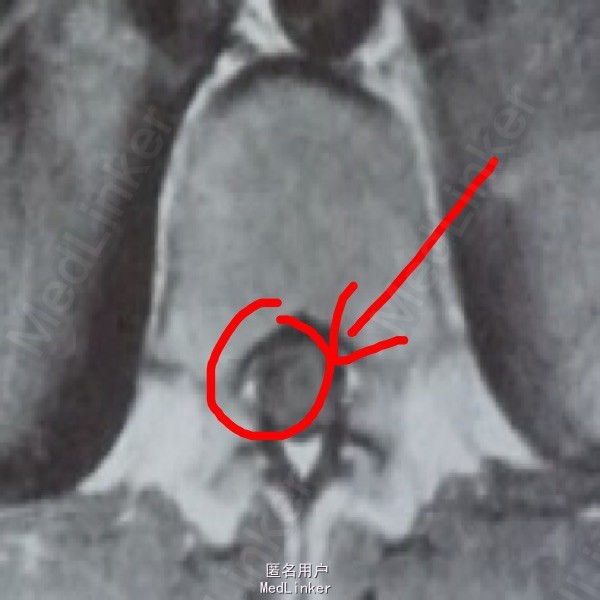

患者,女,32岁。因咳嗽咳痰,背部疼痛一月入院。患者既往有肺结核,一月前感冒后出现咳嗽咳痰,背部疼痛,消炎卧床休息不能缓解。

查体示体温轻度增高,肺部可闻及广泛湿啰音,脊椎无压痛。MRI示椎管内脊髓结构不规则,腰1脊髓对应处有高密度影参杂,密度不均匀。

诊断为肺结核伴脊髓内结核,遂给予抗结核一线药物口服,椎管内注射。